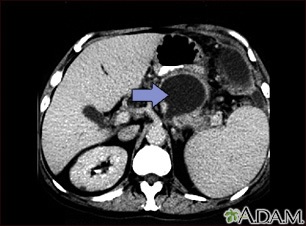

A CT scan of the upper abdomen showing a pseudocyst in the corpus, or tail, of the pancreas.